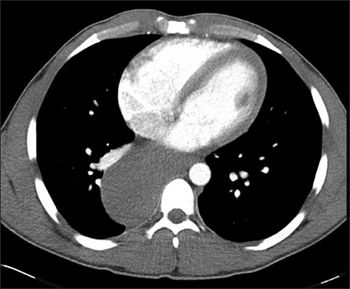

The clinical presentation-crampy abdominal pain after meals, weight loss, and loose stools-is consistent with chronic mesenteric ischemia given this patient's history of diabetes.